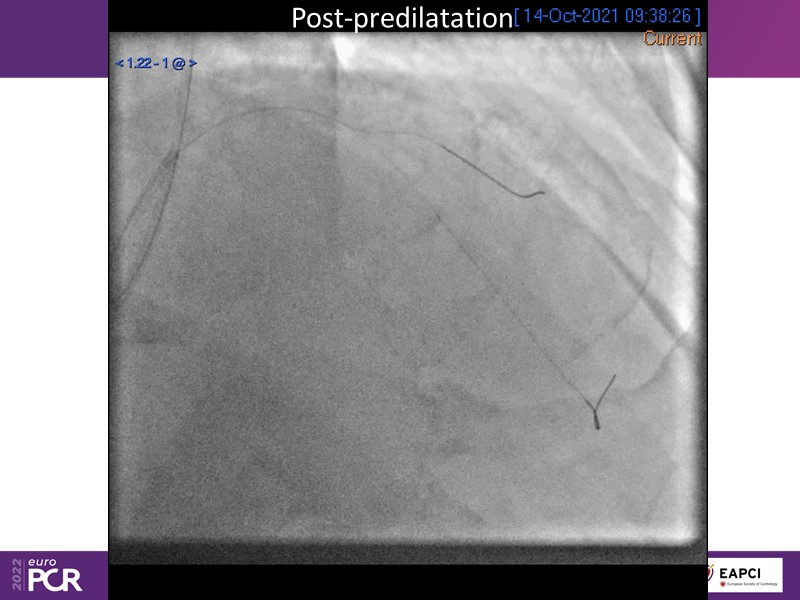

- To find out more about the application and mechanism of a sirolimus coated balloon for coronary artery disease treatment with case presentations in complex settings

- To understand how useful is a DES and DCB stent platform in complex coronary artery disease settings with case demonstrations and follow-up in diabetes mellitus